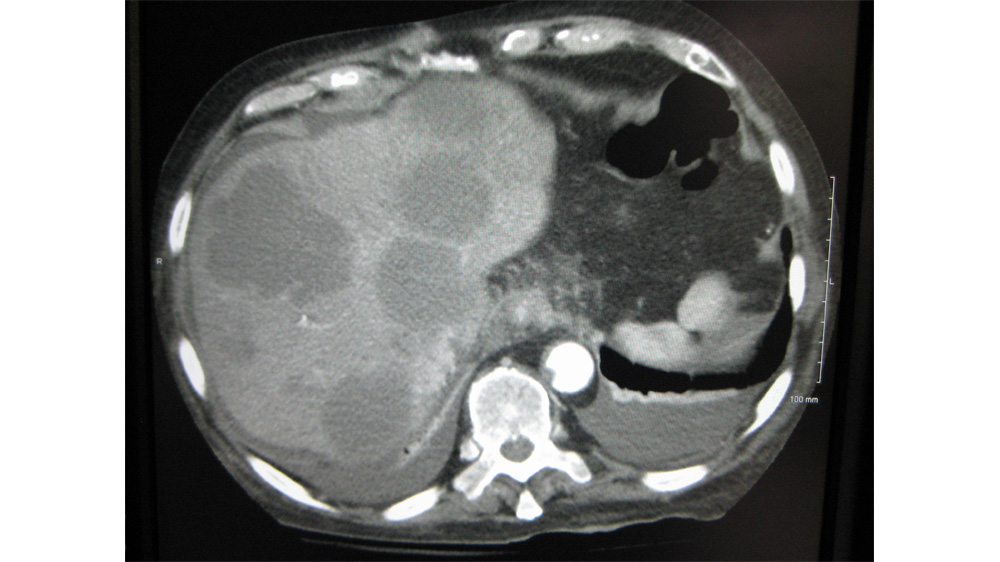

La plupart des cancers du foie primaire sont diagnostiqués par imagerie, mais cela reste un diagnostic complexe. Le foie est également un foyer très fréquent de métastases, en particulier dans le cas des cancers digestifs, dans lesquels près de 50% des patients développent des métastases[5]. Une meilleure caractérisation ainsi qu’une identification précoce de ces métastases peuvent augmenter les chances de guérison.